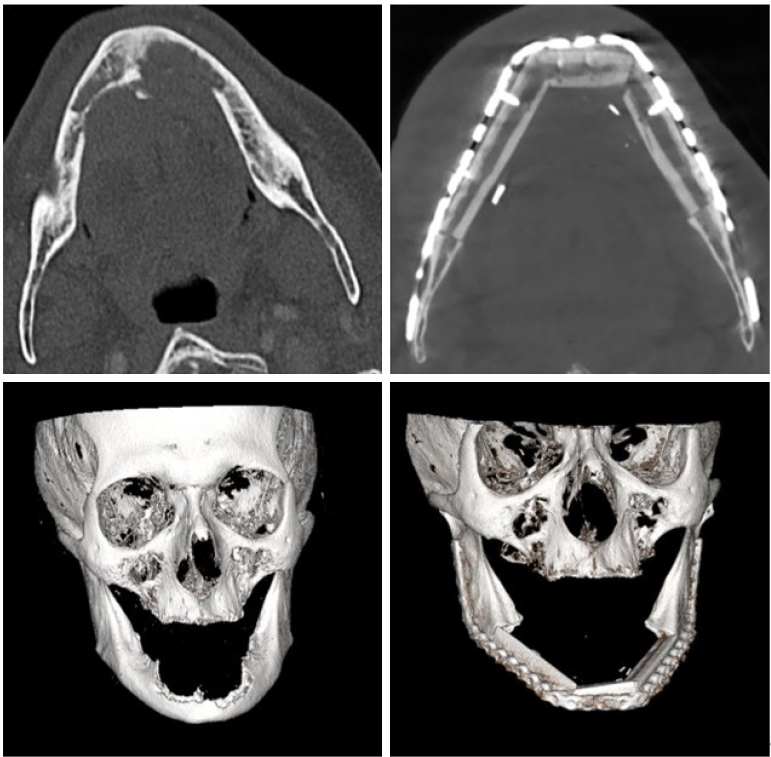

A 77-year-old male patient with diagnosis of SCC of the anterior floor of the mouth infiltrating the mandible and the skin of the chin required a complete surgical excision of the mandible and the soft tissues from intra- to extra-oral [Figure 8]. To reconstruct this extended bone and soft tissue defect, a chimeric FFF was planned combining a long bony part with to skin paddles supplied by different perforators. Using a 3D stereolithographic model (CAD/CAM technology), a reconstruction plate was prebent and used for adapting the free fibula bone graft, which was modeled with two osteotomies in order to mimic the mandible anatomy [Figure 9]. The soft tissue islands were then used to reconstruct the oral defect. Because of the large volume missing on the chin, a second free tissue transfer was required to obtain a good and stable result. For this purpose, we chose a posteromedial thigh (PMT) flap [Figure 10]. The postoperative course was uneventful, a satisfactory functional and aesthetic result was obtained, and no signs of disease recurrence were noted. At four months follow-up, a computer tomography exam was performed, which confirmed a good integration of the fibular bone [Figure 11].

A 63-year-old male presented with a large SCC of the left retromolar trigone with a significant involvement of the mandibular bone and bilateral cervical lymph node metastasis. Because of safety resection margin requirements, we were forced to perform an hemimandibulectomy near the intraoral soft tissue resection. To reconstruct the big defect, we used a chimeric osteocutaneous FFF comprising a bone ready-osteotomized and a skin paddle [Figure 12]. Computer-aided design and manufacturing was used to create a three-dimensional stereolithographic model, which was used to prebend a titan reconstruction plate for fixation and contour of the neomandible. The skin island was used to fill the retromolar soft tissue defect, and the vascular pedicle was then anastomosed to the superior thyroid artery and internal jugular vein. No major or minor microvascular complication occurred, and a computed tomography performed at 17 months confirmed a complete integration of the reconstructed bone [Figure 13].